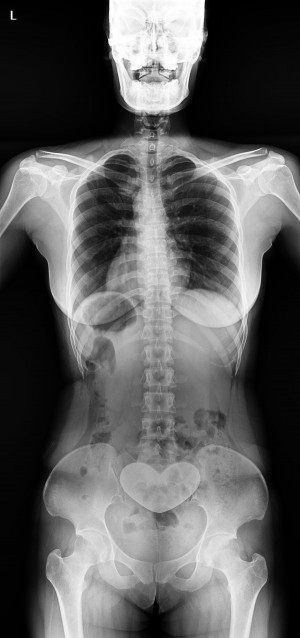

Western Australia, Australia Mar 18, 2021 (Issuewire.com) - Say goodbye to those long waiting times for full spine or leg length studies because within 1 second you can achieve a quick image acquisition with the Longtail – the latest innovative x-ray technology from ATX Medical Solutions. With over 30 years of experience, ATX Solutions has evolved with a profound knowledge of X-ray equipment and its services. The company takes pride in offering a high level of service with unlimited user support to ensure maximum benefits. Recently, a team of experts has initiated the use of this new digital X-ray equipment installed at Capital Radiology in Morley, Western Australia. Clients may ask for the relevance and importance of this newly installed system. Well, to answer their query, Regional Manager at Capital Radiology WA, Joel Scaddan, identified, 3 key features worth mentioning include the following:

So, what does this all mean? In a nutshell, the Longtail digital radiography system delivers the highest image quality, geometric accuracy whilst reducing the amount of radiation with no image overlap received by the patient per diagnostic study. Moreover, practitioners will find it more convenient as they are now able to deliver swift diagnostic results. Managing Director Roger Davis commented the Longtail will supersede existing technologies for full spine imaging systems that are subject to excessive dose, multiple exposures, and software image adjustment techniques that may compromise the diagnosis.